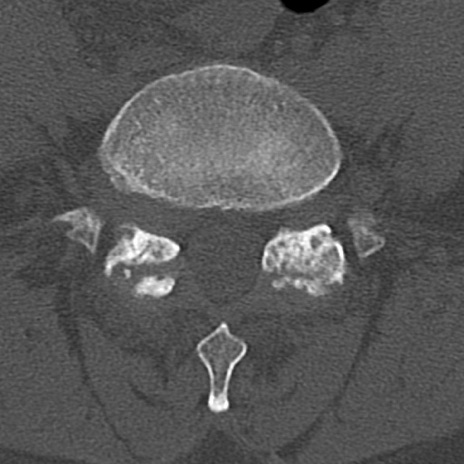

腰椎CT

横断像と矢状断像